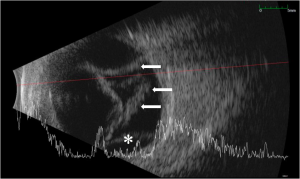

Visual acuity is usually poor and may be count fingers or worse in the setting of a subacute or chronic retinal detachment. Pupillary exam generally reveals a minimally reactive pupil as a result of near-complete or complete (360 degrees) posterior iris synechiae with central iris-lens apposition. Although hypotony is usually seen in these cases, the intraocular pressure may also be normal. Slit lamp examination may reveal a mild to moderate degree of intraocular inflammation characterized by corneal edema (microcystic edema or Descemet’s folds), anterior chamber reaction (cell and flare), and posterior iris synechiae. The anterior chamber is significantly deepened, and gonioscopy reveals a wide open angle due to retrodisplacement of the peripheral iris away from the angle (Figure 1A). The iris body is apposed to the anterior lens face with disappearance of the posterior chamber (Figure 1B). Cataract formation may also result as a consequence of aqueous diversion. Ciliochoroidal detachment or effusions may also be seen especially in the setting of hypotony. Fundus examination and B-scan ultrasonography typically reveal some combination of retinal detachment, choroidal detachment, or PVR if the condition is longstanding (Figure 2). [1][3]

Diagnosis is made via slit lamp biomicroscopy, gonioscopy, fundoscopy, and B-scan ultrasonography. Ultrasound biomicroscopy may also provide greater detail of anterior segment structures in the setting of iris retraction syndrome. [10]